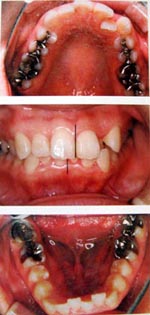

子供の例

狭く細長い歯並び

舌が収まりきれず、気道を圧迫し、いびきや無呼吸症候群の原因となります。

このような顎が小さい場合に装置は適応されます。

矯正後

1日10時間程度、自宅で装置を使い、本来の位置まで成長させると自然に歯が並びます。また、空間ができて、いびき、無呼吸症候群が解消します